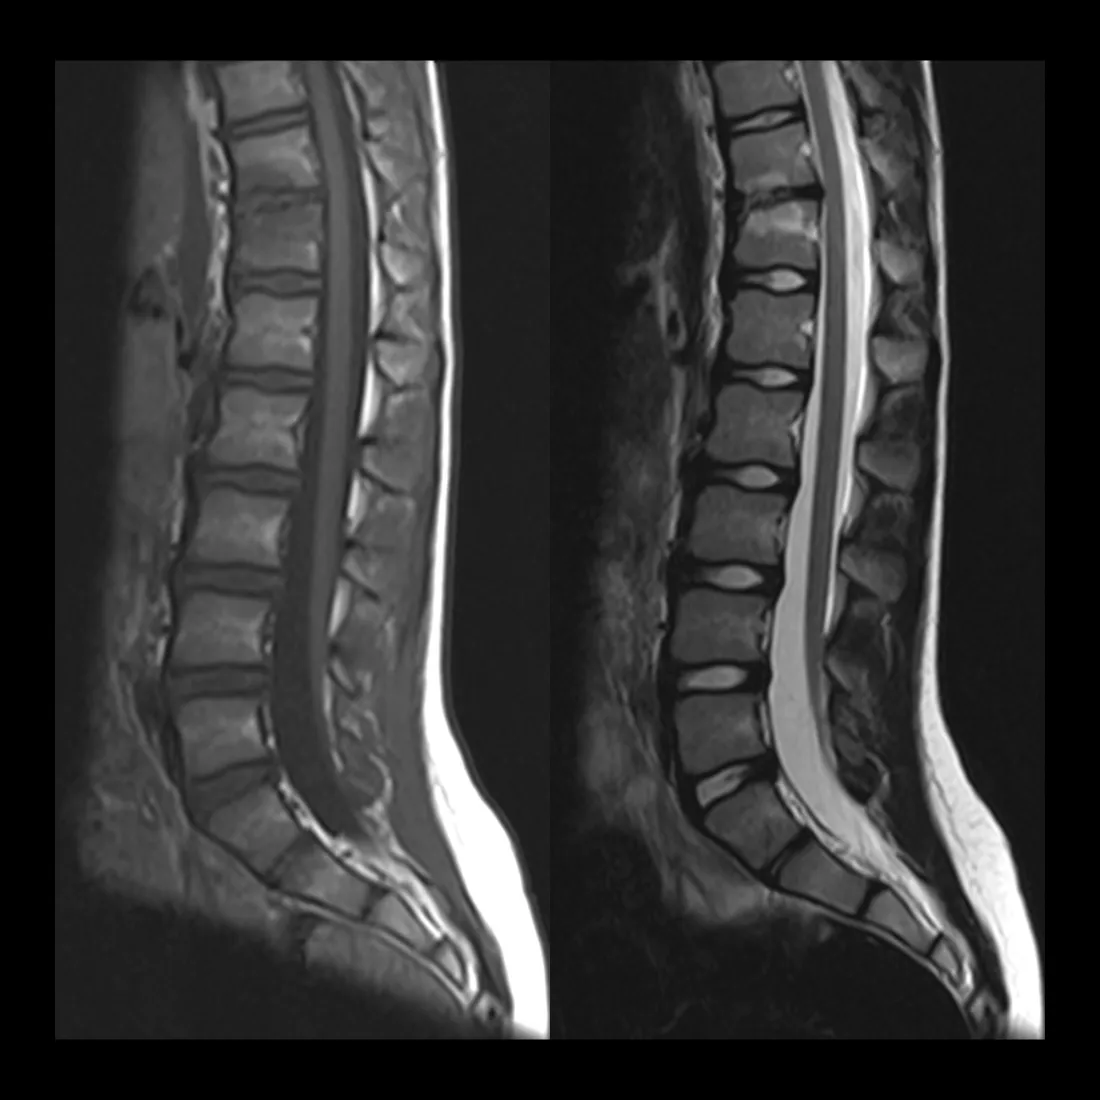

What was the tethered cord MRI about?

Before surgery, Dr. Lee wanted an MRI of my lower spine to check for a tethered cord, the idea being that if I had one, they could potentially do both surgeries at the same time. But VA insurance made it nearly impossible to turn that around before my surgery date.

So during my stay, they came back to me and said: since you're already here and everything is under the same VA referral, we'd like to get that MRI now. They were seeing symptoms that could be coming from a tethered cord, and if that was the case, they wanted to operate. The MRI came back clear. No tethered cord.